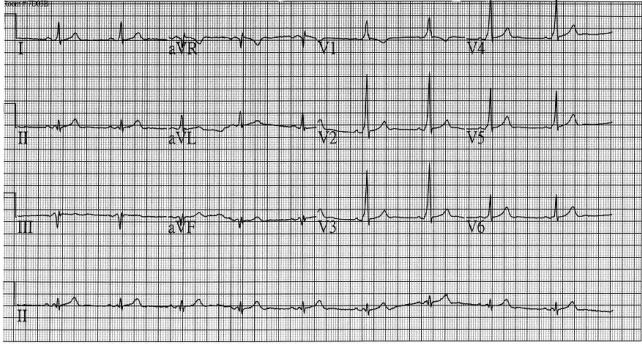

37.一位46歲女性因為常常頭暈,爬樓梯時感到很喘而來醫院求診。身體檢查除臉⾊與結膜蒼白之外,並無其他 明顯異常。患者血壓106/76 mmHg,脈搏每分鐘72次,規則心跳,無發燒,亦無體重減輕或是食慾降低的現 象。血液數據顯示血紅素7.6 g/dL,白血球4,030/μL,無異常分類,血小板418,000/μL,MCV 74.8 fL(參考 區間80~100),ferritin 3.84 ng/mL(參考區間28~365),serum iron 10 μg/dL(參考區間51~209), TIBC(total iron binding capacity)459 μg/dL(參考區間268~593)。血液抹片如下圖所示。有關這位病人 最可能的疾病之描述,下列何者錯誤?

(A)此類病人的血液中的reticulocyte counts常是降低的 (B)此類病人的骨髓中的sideroblast比例常是降低的 (C)此類病人的紅血球中的protoporphyrin 量常是降低的 (D)此類病人的red cell distribution width(RDW)index常是增加的